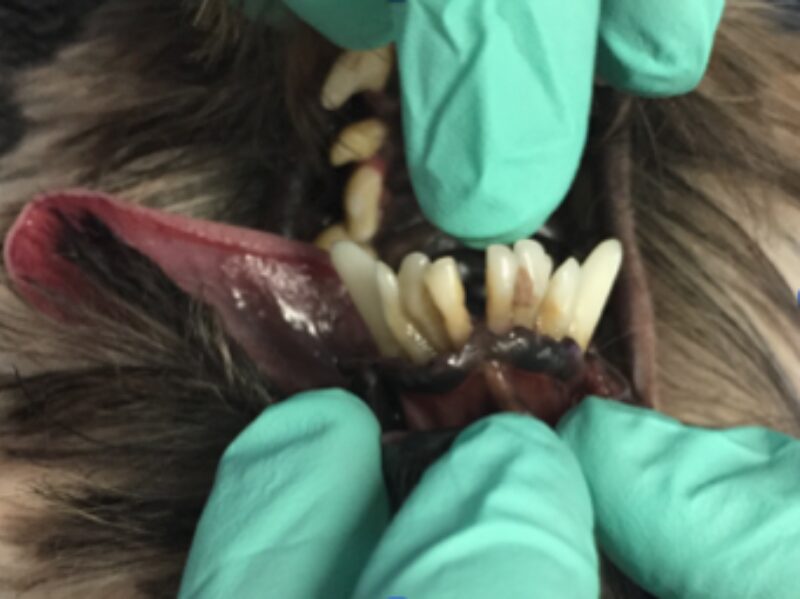

Als ich bei Leila ins Maul schaute, staunte ich schon nicht schlecht. Ich sah die Besitzerin an und fragte: „Wie alt war Leila noch mal?“ Leila war tatsächlich erst drei Jahre alt und doch wusste ich da schon, dass wir wahrscheinlich keinen Zahn retten könnten. Man sieht es wirklich nur, wenn man etwas genauer hinschaut: Leilas Zahnhälse lagen alle frei, und eitrige Beläge kamen aus der Tiefe des Zahnfachs (Abb. 2 - 5).

Solche Veränderungen treten oft bei einer hochgradigen Parodontitis auf. Eine Parodontitis ist die Entzündung des gesamten Zahnhalteapparates (also des Kieferknochens, des Zements, der Paradontalfasern und des Zahnfleischs) und wird durch die Bakterien, welche im Plaque enthalten sind, hervorgerufen. Diese zerstören die Anheftung der Gingiva am Zahn, und die Bakterien können bis zur Wurzel vordringen. Hier rufen sie Entzündungsreaktionen des Kieferknochens und der Gingiva hervor, wodurch beide sich zurückziehen und tiefe Paradontaltaschen entstehen lassen. Doch Leila hatte, wie auf den Bildern schön zu sehen ist, kaum Zahnstein oder Plaque.